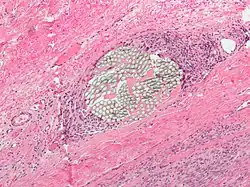

Peritoneum

Foreign bodies in the peritoneum can include retained surgical instruments after abdominal surgery. Rarely, an intrauterine device can perforate the uterine wall and enter the peritoneum.

Foreign bodies in the peritoneum eventually become contained in a foreign body granuloma. In the extremely rare case of retained ectopic pregnancy, this forms a lithopedion, which involves the fetus being too large to be reabsorbed, and is calcified[13] as a means of shielding the surrounding tissue from infection.